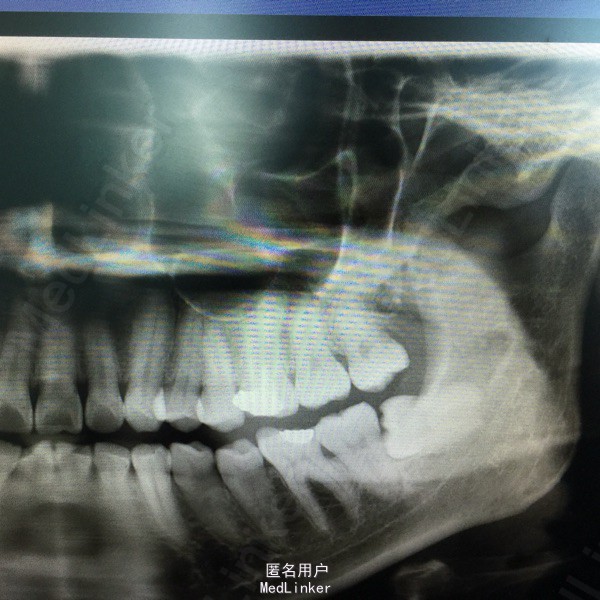

随访:患者术后一周复查述:左下唇自觉轻微麻木。复查全景牙片见:38近中根尖拔牙创周骨质塌入下牙槽神经管1mm。予以口服营养神经药物,其无需特殊处理。一个月后述下唇麻木感消失,无其它不适感。 讨论:下颌近中水平阻生的拔除,应注意与下牙槽神经管的关系,分析阻力,避免暴力拔牙。